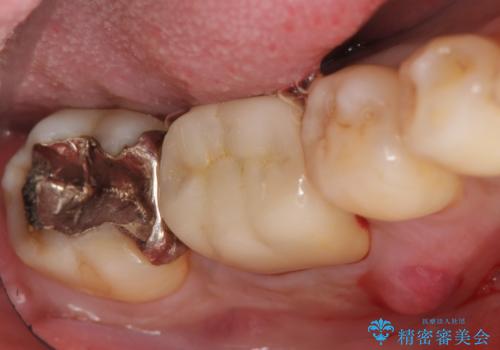

- 数か月前から右下の奥歯の歯茎から膿が出る、他院で相談したところ抜歯といわれたが何とか残せないか診て欲しいといらっしゃった方の症例です。

再根管治療を行い、フィステル(膿の出口)の消失および根尖病変の縮小を確認後、オールセラミッククラウンによる補綴を行いました。